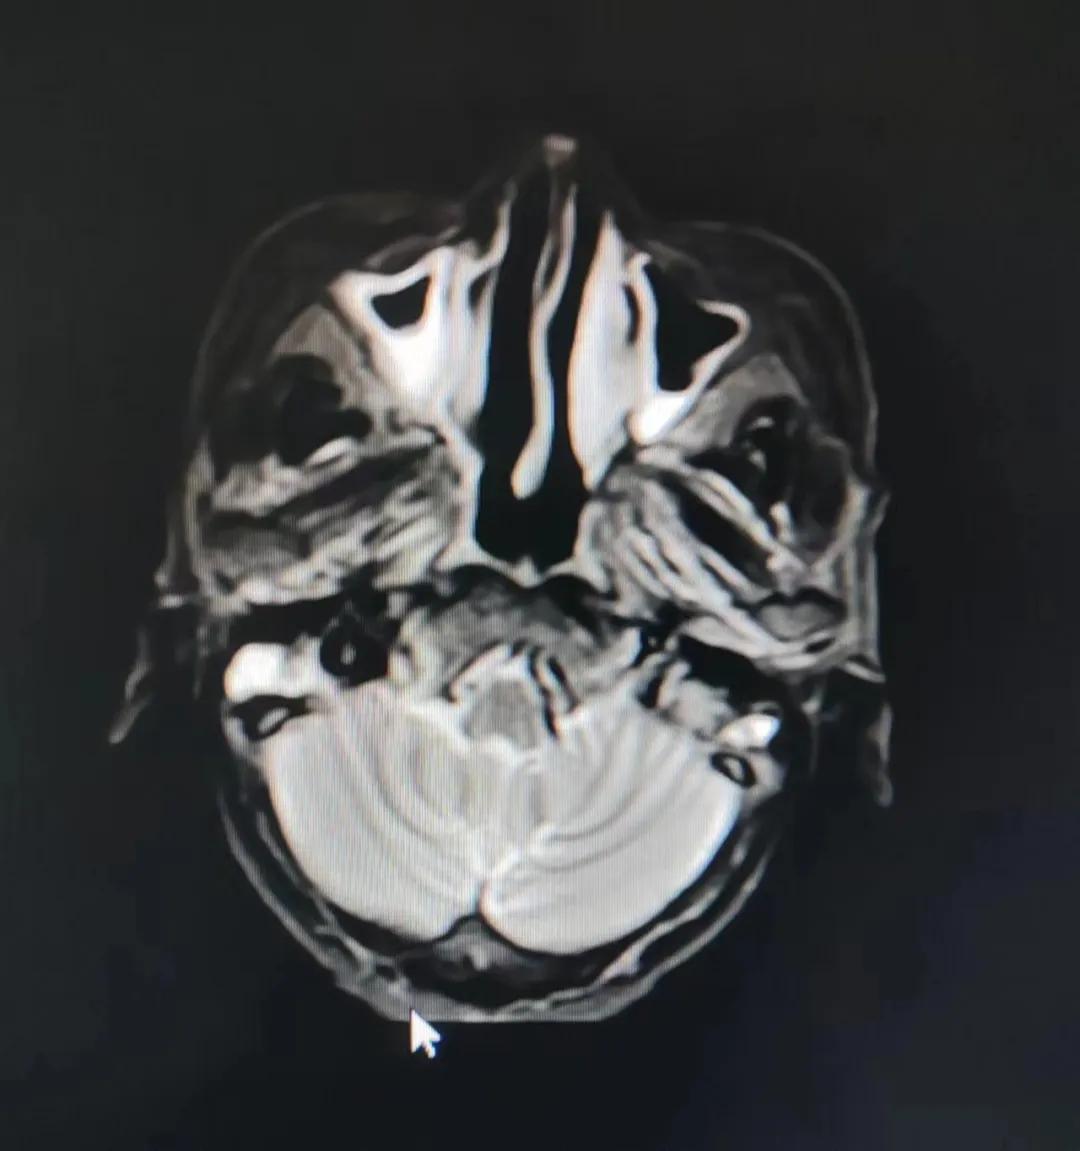

治療后

放療結(jié)束,除了放療處的皮膚輕微放射性皮炎外,基本沒(méi)有什么不良反應(yīng)。復(fù)查發(fā)現(xiàn),鼻腔淋巴瘤已不可見(jiàn),目前患者已康復(fù)出院。